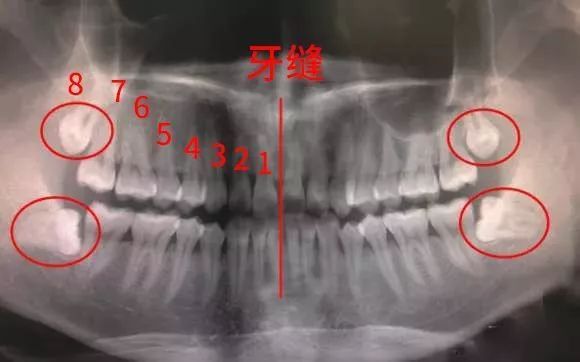

智齿,一般是于16岁或之后才生长出来,是在人类心智已经趋于成熟时才长出,因而得名。有调查表明:我国16~25岁人群中智齿的萌出率为54%,在已萌智齿中阻生和错位约占44%。(图中画圈的地方为智齿)由于智齿因萌出位置不足,牙齿可能部分或全部被龈瓣覆盖,加上位于口腔的最内侧,刷牙的时候难以清理到,细菌滋生引发智齿冠周炎,导致咀嚼、吞咽,开口活动疼痛加重。到了冠周炎的中后期,表现为口臭、舌苔变厚、智齿周围流脓等症状,甚至半边脸都会肿起,口张不开,不能进食,可以伴随发烧、头痛、便秘,淋巴结发炎肿大等。关于智齿的这些问题你是不是也疑惑过我的智齿前几天肿痛得厉害,这两天又不痛了,可以不拔嘛?我看我朋友那智齿发炎了,半个脸都肿了,别说他疼了,我看着都疼,感觉自己嘴里长了一个定时炸弹,不知道什么时候就会爆发,到底该不该拔?.....很多人对于要不要拔智齿总是很犹豫其实智齿跟聪明搭不上边还是一颗分分钟可能引爆的“定时炸弹”哪些智齿一定要拔掉通常医生会基于以下几点理由:建议拔掉智齿智齿蛀牙智齿出现比较深的龋坏(也就是俗称的虫牙、蛀牙),或位置不正、窝洞发生在牙齿邻面、位置较深等,日常刷牙很难清洁到,这种也建议拔掉,否则可能引发神经痛、牙髓炎。智齿挤压邻牙通常患者不自知,而由牙医以X光诊断得知。智齿萌发的空间不足,会倒在下颌第二磨牙上,造成下颌第二磨牙清洁不易,造成两颗牙之间的牙槽骨吸收的现象,引起进食时食物嵌塞或牙疼。智齿反复发炎智齿是牙列中最后萌出的牙,因萌出位置不足,牙龈与牙体之间形成一个狭窄较深的盲袋,容易积存食物碎屑和细菌,不易清洁,诱发智齿冠周炎。没有咬合功能的智齿上下颌智齿并非成对萌出,如果上下没有相抗衡的智齿来对咬的话,有时会发生智齿会“伸长”,影响咬合。正畸需要拔出智齿为了排齐牙齿腾地方,保证正畸治疗的效果,通常会考虑拔除智齿或其他不是那么重要的牙。如果是智齿挤占空间导致其他牙齿错位、变形,那就更得拔了。埋伏的智齿完全埋伏在颌骨内无法萌出的智齿,病人不一定有感觉,这类智齿像一颗“定时炸弹”,随时会引发炎症或影响周边牙齿健康,且有造成颌骨囊肿的风险。但并非所有骨埋伏的智齿都需要拔除,有些埋伏较深,拔除的风险及并发症较多,但又没有挤压邻牙,发生囊肿概率低的智齿,建议定期观察。什么样的智齿能够保留?位置比较正,正常萌出的,并且有正常咬合,能清洁到位的智齿,无龋坏,冠周软组织没有发炎和疼痛史;口腔内第一第二磨牙过早缺失,可以以正畸或者牙移植的方式将智齿移动到缺失牙的位置发挥功能。这类人最应该拔智齿女性怀孕以后由于激素水平升高和糖分摄入量增加,智齿冠周炎以及邻牙龋坏相对多发,孕早期的冠周炎除了冲洗治疗以外,抗生素根本不能用,只能靠孕妇死扛,能扛过去的还好,扛不过去的就极其悲催。一位孕妇智齿冠周炎并发颌面多间隙感染的病例,入院不久即因呼吸困难转ICU紧急气管切开并同时剖腹早产一婴儿,虽母子双保,但教训深刻。智齿对孕妇的危害实在太大,请广大备孕女性趁早拔掉智齿,尤其是前倾阻生智齿。这些人群应暂缓拔牙半年内有心梗病史,心绞痛频繁发作,心功能III-IV级,高血压患者(血压控制不佳),造血系统疾病、糖尿病血糖空腹大于8.88mmol/L的患者,还有月经期女性、急性肝炎、肾脏疾病、甲亢功能异常等人群;长期使用抗凝药物和感染期间的,都要暂缓拔牙。拔智齿到底痛不痛广大年轻人,仍然因深入骨髓的牙科恐惧症而拒绝拔智齿,最主要是怕痛。拔智齿到底痛不痛呢?这个和医生的技术,麻药的选择,患者的疼痛耐受阈值都有关,但是一般来说稍有疼痛但可以耐受。二十年前情况稍差,那时常规的口腔局麻药物是利多卡因,效果因人而异。现如今口腔医疗已经大有改善,进口局麻药”阿替卡因肾上腺素注射液“和“盐酸甲哌卡因注射液”早已成为所有牙科的常规首选,口腔镇痛效果卓越。所以只要发现智齿有问题,越早治疗越好,痛苦一周,幸福一辈子